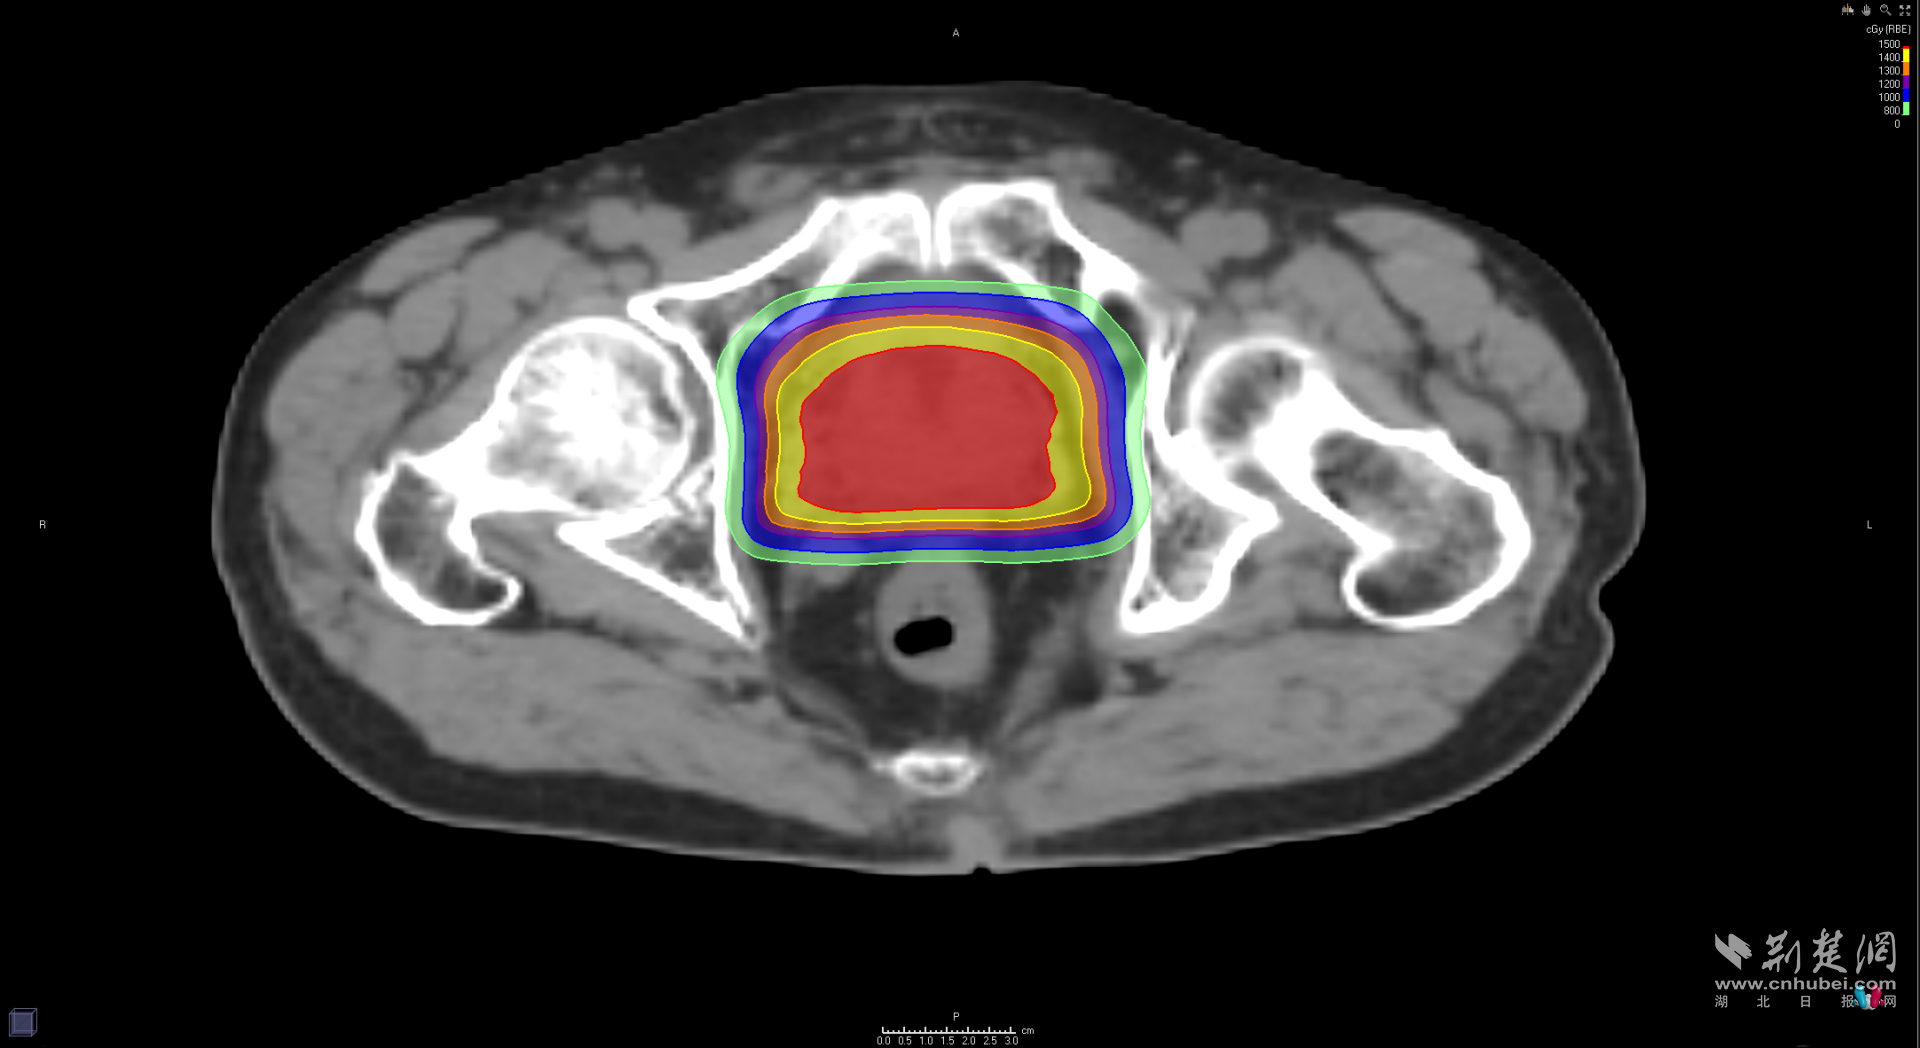

图为患者质子放疗靶区剂量分布图,直肠区域几乎无高剂量射线照射

在凝胶“防火墙”的悉心保护下,真正的“重头戏”——质子超大分割放疗正式登场。“不用紧张,每次治疗就几分钟,躺着不动就好。”治疗师轻声安抚着杨大爷。随着设备启动,无声的质子束精准锁定肿瘤目标。与传统放疗需要“跑”二三十次、持续一两个月的漫长过程不同,此次治疗采用“超大分割”技术,将总剂量分成几次“猛药”,在一周内完成5次治疗,实现了精准高效的治疗效果。